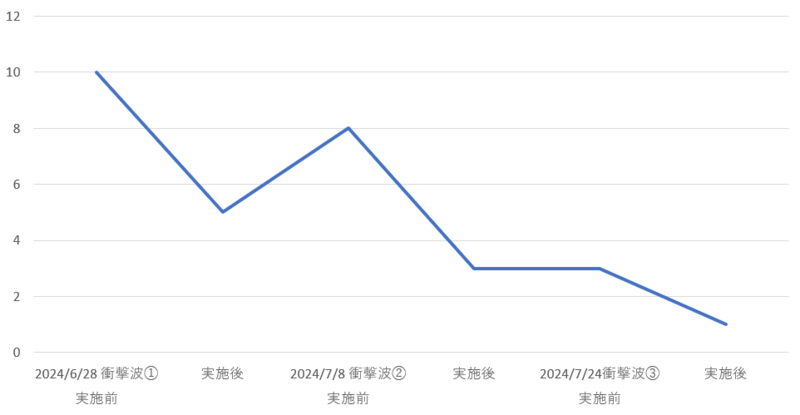

【疼痛推移】

下に治療中の疼痛推移を示します。

体外衝撃波は3回施行し、漸減的に疼痛が軽減していきました。

制限なく趣味のフットサルに復帰できたため通院終了となりました。

縦軸:痛みの強さ 最も痛い:100 痛くない

横軸:時間軸